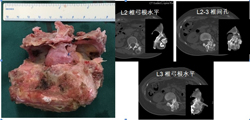

图3-7,后路肿瘤切除照片显示肿瘤切除后T12,L1至L4,L5椎弓根螺钉固定,L1-3椎体间钛网植入,左侧L2神经根切除。

图3-8,术后标本,标本CT平扫与术前图像对比,显示整块肿瘤切除的范围,切除边界充分。

图3-9,术后X片及CT显示肿瘤切除后内固定重建。

术后病理证实:高分化软骨肉瘤。病人术后左侧髂腰肌肌力减弱,其余下肢肌力5级;术后7天下地活动,可走平路。术后3个月复查时左下肢肌力基本正常,病人可正常行走。术后随访33个月,肿瘤无复发,内固定稳定。